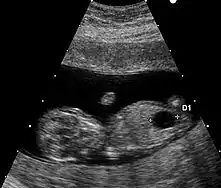

Les anomalies échographiques sont également prises en compte. Il s'agit de la recherche de malformations classiques de la trisomie 21 (comme les malformations cardiaques) et aussi de «marqueurs dont le plus important est l'épaisseur de la clarté nucale. D'autres signes sont discutés car difficiles à mesurer avec des résultats variables selon les observateurs. Toutefois, à la fin des années 2000, la combinaison entre la mesure de la clarté nucale et l'âge maternel est considérée comme un marqueur puissant d'une probabilité de trisomie 21[38].

Jusqu'en 2017, si la probabilité calculée est supérieure à 1 sur 250, un examen à visée diagnostique, invasif, (amniocentèse) était proposé à la femme enceinte pour analyse du caryotype fœtal (diagnostic prénatal par ponction de liquide amniotique à partir de 19 semaines). Lorsque l'âge gestationnel est très avancé (vers la 30e semaine) un prélèvement de sang fœtal en ponctionnant le cordon ombilical peut être réalisé.